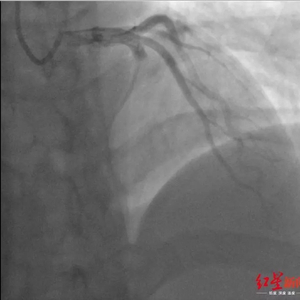

小蒲术前的冠脉造影显示 前降支血管严重堵塞

大量的血栓造成堵塞,介入医生用导管反复抽吸血栓,“大大小小一共10块,最大的一块把导管都堵了,我们只能把导管全部退出来,重新再进一次,反复抽吸。